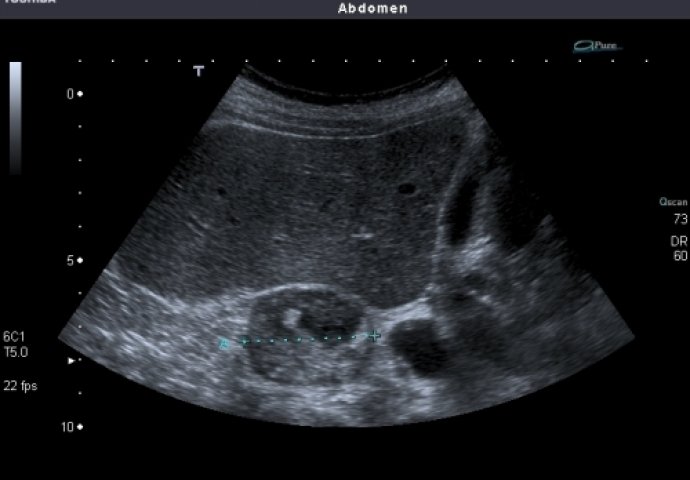

Konačno, tumor nadbubrežne žlijezde može izazvati i pojačano lučenje adrenalina što vodi u visok krvni pritisak, slabost i grčeve u mišićima. Nekada se adenom otkrije tek kada počne da pritiska okolne organe. Tada se dijagnoza može postaviti jedino ultrazvukom nadbubrežne žlezde u lekarskoj ordinaciji.